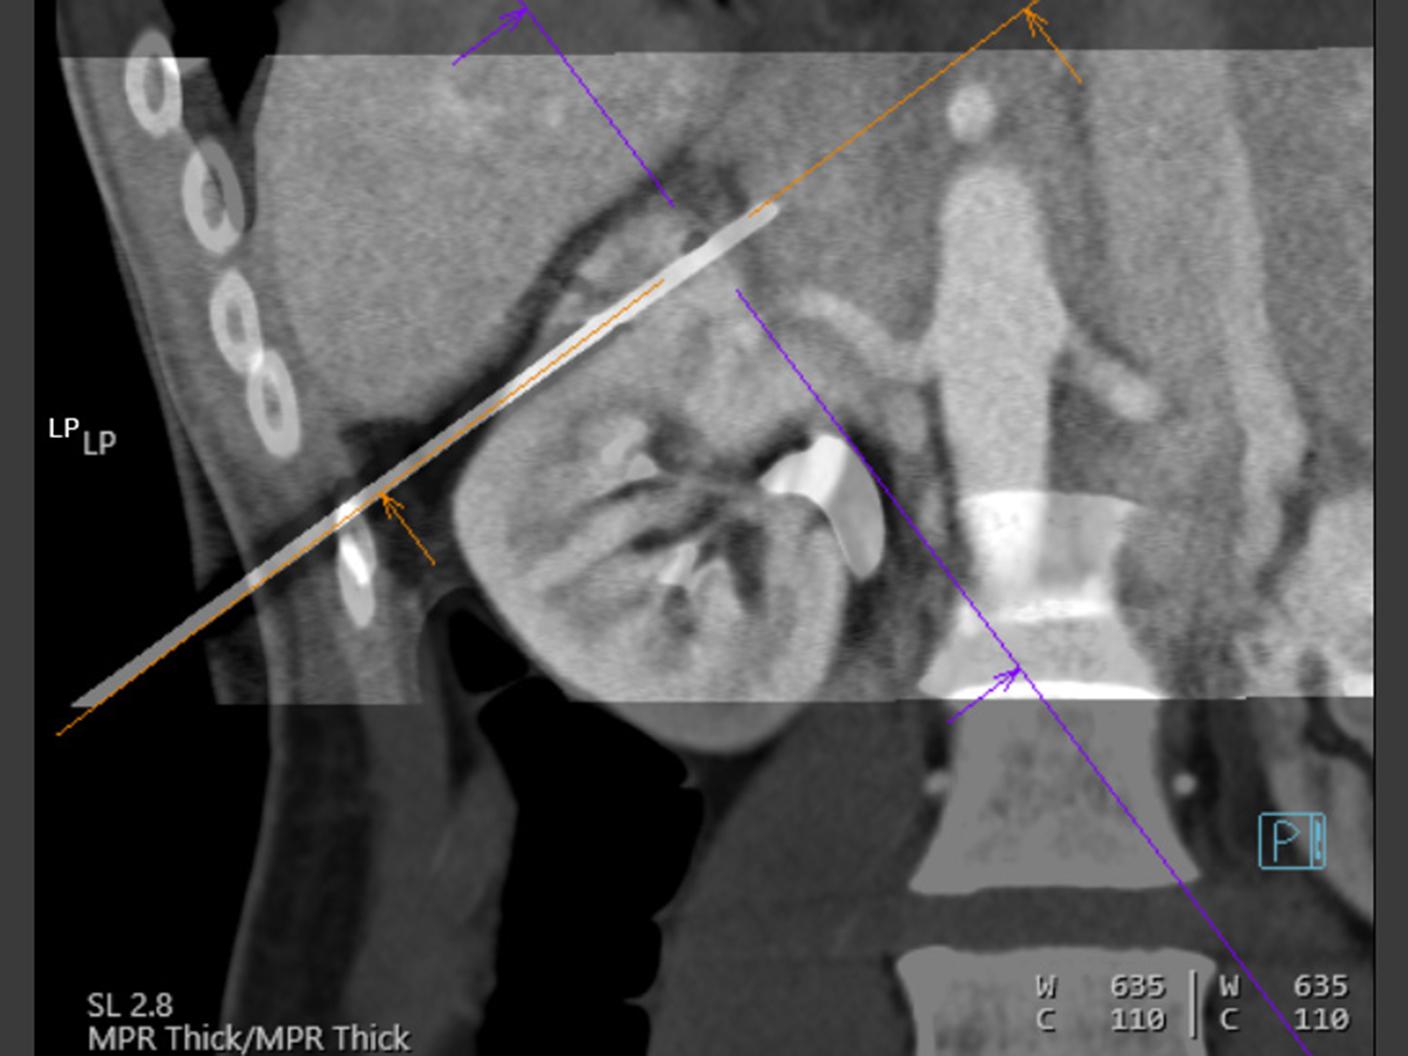

At the heart of NAEOTOM Alpha® is a radically new photon-counting detector. The QuantaMax detector directly converts X-rays into an electrical signal, which is then used to create an image. The energy of each X-ray is measured, so spectral information is available for every scan, and the images are contrast-rich with high spatial resolution at the same dose. Combining the high spatial resolution of the QuantaMax photon-counting detector with our Dual Source temporal resolution enables the visualization of fine details for increased diagnostic confidence.